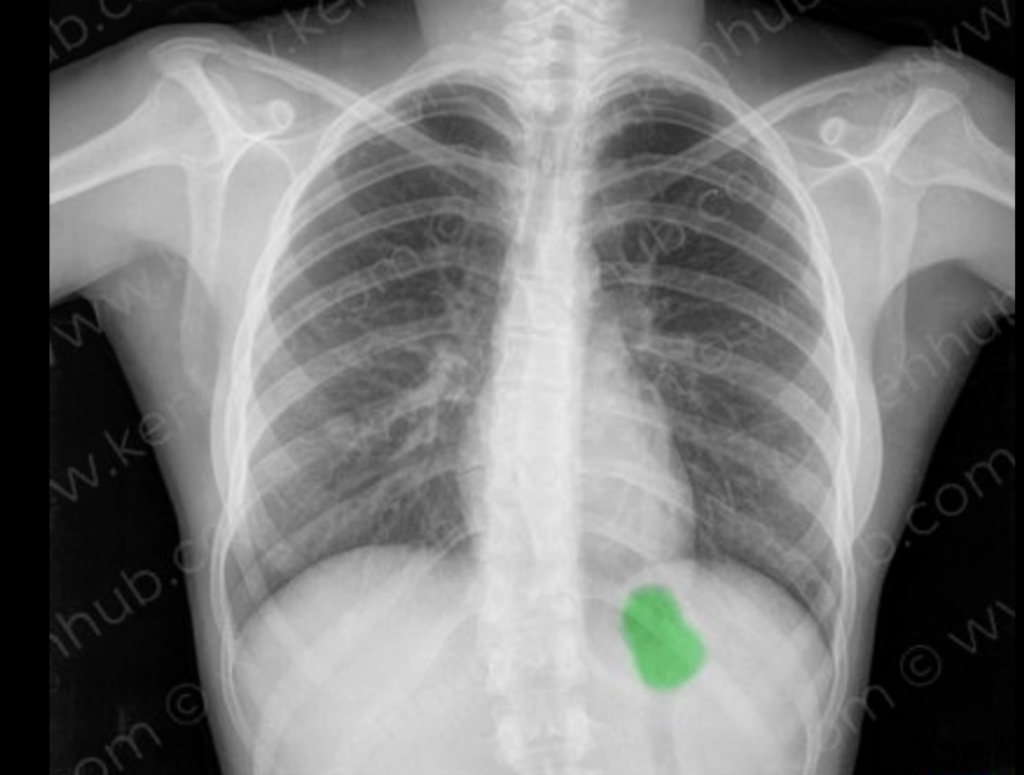

Durante su intervención, Jiménez detalló cómo se adaptan los procedimientos para minimizar la exposición, especialmente cuando se trata de estudios como radiografías de extremidades o tomografías que no involucran directamente la región abdominal.

- El experto añadió que el uso del delantal o peto plomado sobre el vientre es obligatorio en estos casos, como parte de los mecanismos de protección que aseguran una exposición mínima y cumplen con los estándares internacionales.

“En este caso, entonces, pondríamos a la paciente eh le colocaríamos el peto o el delantal plomado sobre su vientre, sobre sobre donde se encuentra el producto y de esa manera podemos trabajar de de de forma eh segura y eh eficiente para poder diagnosticar esa lesión que tenga esa paciente. Okay.”